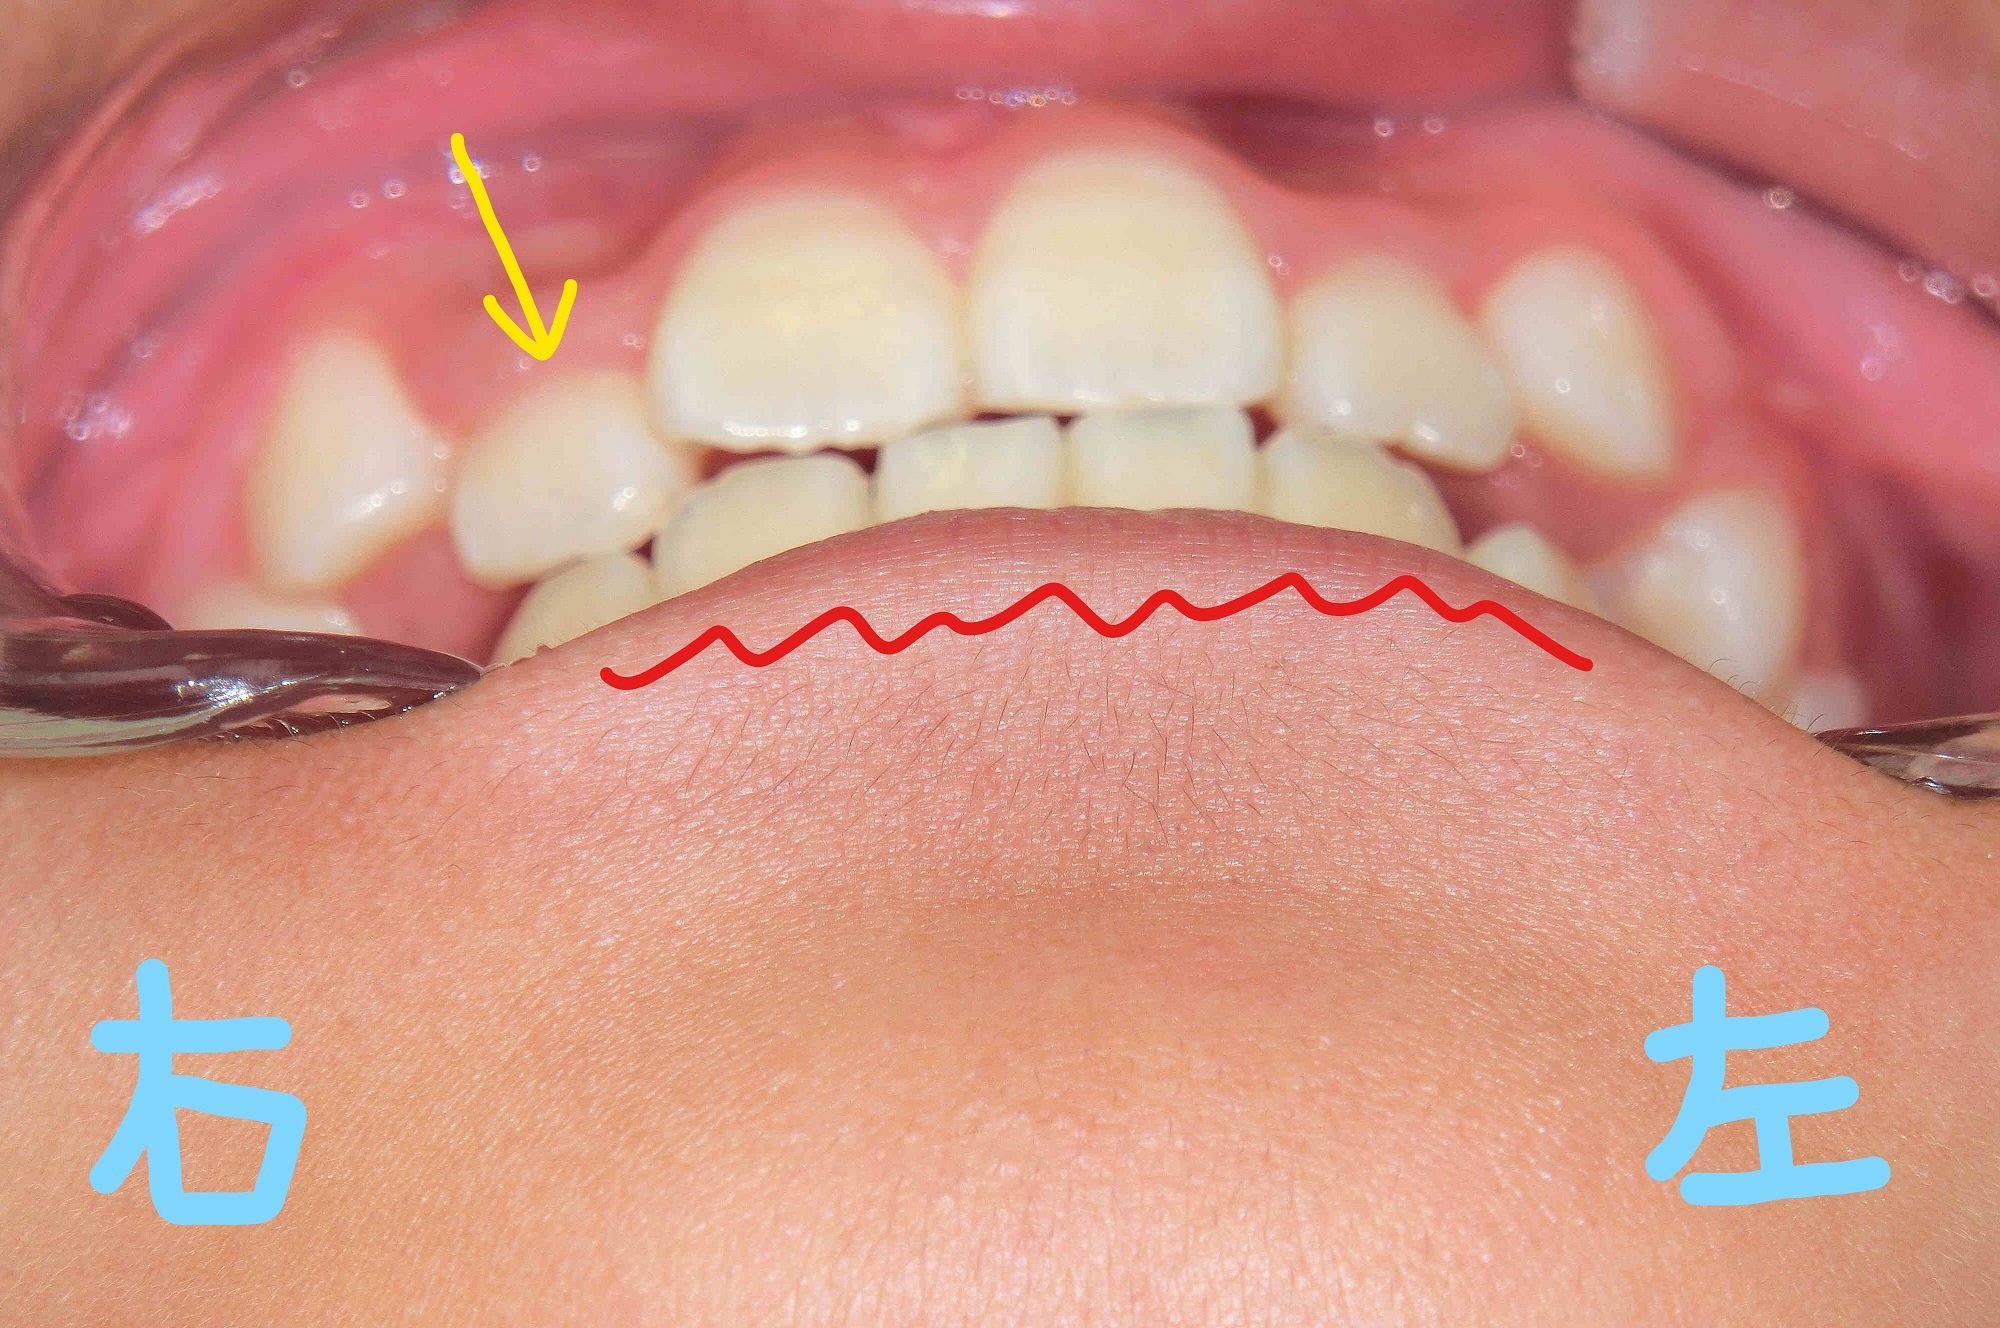

左上の写真は正面から、右上は下から見上げた角度の口腔内写真です。初診時には内側に位置していた右上前歯(黄色矢印の歯)が、上顎歯列の拡大によって前方に誘導されている様子が確認できます。また、下顎前歯(赤色波線部分)の叢生(いわゆるガタガタの歯並び)にも改善傾向が見られます。